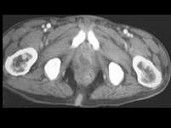

- 多项选择题男,35岁, 右侧腰部疼痛伴发热,根据所示图像, 最可能的诊断是 ( )

A、右侧肾脓肿

B、右侧单纯性肾囊肿

C、右侧囊性肾癌

D、右肾转移癌

E、前列腺脓肿